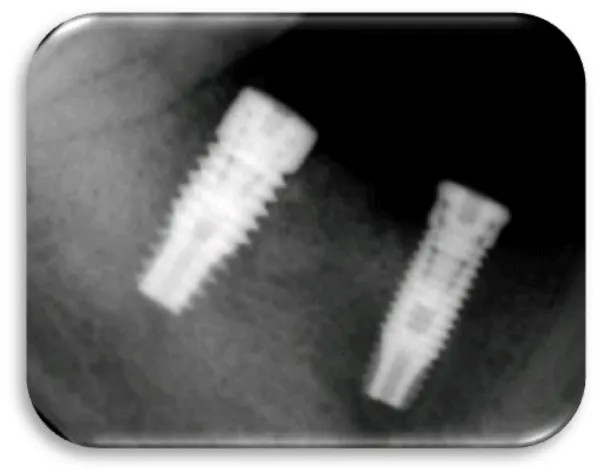

The eighth clinical case is a female 42 year old patient, which is in good health and with good oral hygiene habits. Before a 9-months, she received two titanium dental implants. The position of the placed dental implants were in the mandible, in the posterior right quadrant. The dental implants were placed due to the missing of the second premolar and the first mandibular molar. A control X-ray image was made to the patient because of the suspicion that she has a peri-implant disease. In the clinical examination, it was found that the gingiva around the dental implants was swollen and hyperemic. The impressions and minimal bleeding were observed on the gingival palpation. The bleeding from the gingiva occur during the process of probing, and pocket depth of 3.5 mm was detected. After the performed x-ray examination, a very small marginal bone resorption was detected аnd no surgical intervention was required (Figures 30-32).

Woman at aged 37 year age, in good health condition and without any systemic diseases, allergic to penicillin came for prosthetic rehabilitation. She was without second premolar and first molar in the lower right quadrant. The patient was provided with dental implants at 45 and 46 (Figures 17-19). After a month on a 45-implant, retrograde peri-implantitis appeared. In chronological order, X-ray images are shown on figures from 17 to 20.

Different treatment strategies were performed in order to remove peri-implantitis. Provided treatment include: debridement of bone tissue, use of bone grafts from known biocompatible grafting materials, i.e. BioOS, disinfection of the surface of the dental implant. After 12 months, another radiography record was made, where ceramic crowns over the implants were seen and there was no longer peri-implantitis (Figure 20) [19,20].